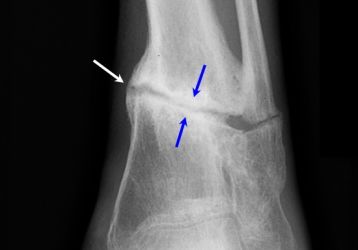

Особенности диагностики и лечения остеоартроза суставов стопы

Диагностика симптомов остеоартроза стопы. Причины заболевания. Медикаментозные и хирургические способы лечения мелких суставов.